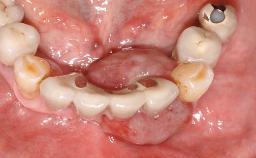

Surgical treatment of a 67-year-old male patient exhibiting an extended edentulous space in the anterior maxilla after the removal of three hopeless incisor teeth.

The video demonstrates implant placement using a surgical stent according to the principle of prosthodontically driven implant placement. The deficient ridge is augmented with locally harvested autologous bone chips, a superficial layer of xenogenic DBBM particles and a resorbable collagen membrane. The surgery is completed with a precise, tension-free primary wound closure.

Case Type Extended Space

Jaw Maxilla

Area Anterior

# of Teeth 4

# of Implants 2

Soft Tissue Anatomy Intact Defective

Bone Volume Horizontally and vertically sufficient Horizontally deficient Deficient vertically or deficient vertically AND horizontally